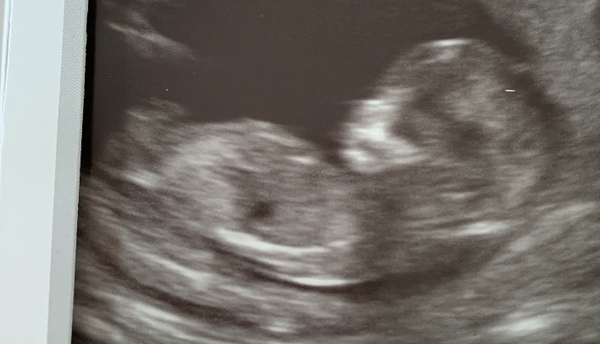

november90 · 31/10/2019 07:33

@lovepositivity I would say boy!

Beautiful scan photo 💗

Hayley220 · 31/10/2019 13:18

Hi everyone! Just wanted to update I had my scan Monday and all was well. Down syndrome risk 1 in 4700 and Edwards and Pateaus 1 in 10,000. Will insert a photo what do you all think from the nub boy or girl? Xx